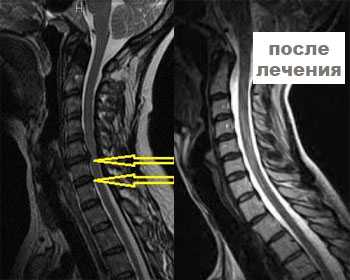

Магнитно-резонансная томография шейного отдела позвоночника и головного мозга для постановки диагноза и выбора оптимального варианта лечения.

Головные боли, шейный остеоходроз и грыжи позвонков. По итогам лечния - уход головных болей, уменьшение болезненности шейного отдела. По снимкам-восстановление околопозвоночных тканей, уменьшение грыжи.